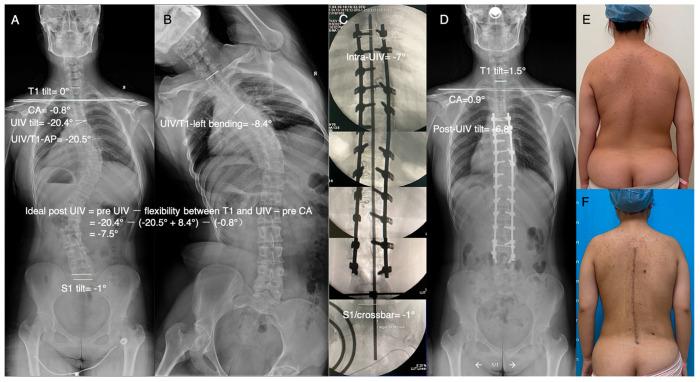

Lateral shoulder imbalance (LSI) is reflected radiologically by the clavicle angle (CA). How to achieve postoperative lateral shoulder balance (LSB) after scoliosis correction surgery remains unclear. In the current study, by using the preoperative upper instrumented vertebra (UIV) tilt, the CA, the flexibility between T1 and the UIV, and the ideal postoperative UIV tilt was predicted based on the following formula: ideal postoperative UIV tilt = preoperative UIV tilt-the flexibility between T1 and UIV-preoperative CA. The reliability of the formula was verified through a retrospective analysis, and 76 scoliosis patients were enrolled. The feasibility of this method was verified through a prospective analysis, and 13 scoliosis patients were enrolled. In the retrospective study, there was a significant correlation between the difference in the actual and ideal postoperative UIV tilt values and the postoperative CA, with correlation coefficients in the whole, LSI, and LSB groups of 0.981, 0.982, and 0.953, respectively ( < 0.001). In the prospective study, all patients achieved satisfactory LSB. Using the formula preoperatively to predict an ideal postoperative UIV tilt and controlling the intraoperative UIV tilt with the improved crossbar technique may be an effective digital method for achieving postoperative LSB and has important clinical significance.

肩部外侧失衡(LSI)在影像学上通过锁骨角(CA)反映出来。脊柱侧弯矫正手术后如何实现术后肩部外侧平衡(LSB)仍不清楚。在本研究中,通过术前上固定椎(UIV)倾斜度、CA、T1与UIV之间的柔韧性,并基于以下公式预测理想的术后UIV倾斜度:理想的术后UIV倾斜度=术前UIV倾斜度-T1与UIV之间的柔韧性-术前CA。通过回顾性分析验证了该公式的可靠性,纳入了76例脊柱侧弯患者。通过前瞻性分析验证了该方法的可行性,纳入了13例脊柱侧弯患者。在回顾性研究中,实际与理想术后UIV倾斜度差值与术后CA之间存在显著相关性,全组、LSI组和LSB组的相关系数分别为0.981、0.982和0.953(<0.001)。在前瞻性研究中,所有患者均获得了满意的LSB。术前使用该公式预测理想的术后UIV倾斜度,并采用改良横杆技术控制术中UIV倾斜度,可能是实现术后LSB的一种有效的数字化方法,具有重要的临床意义。